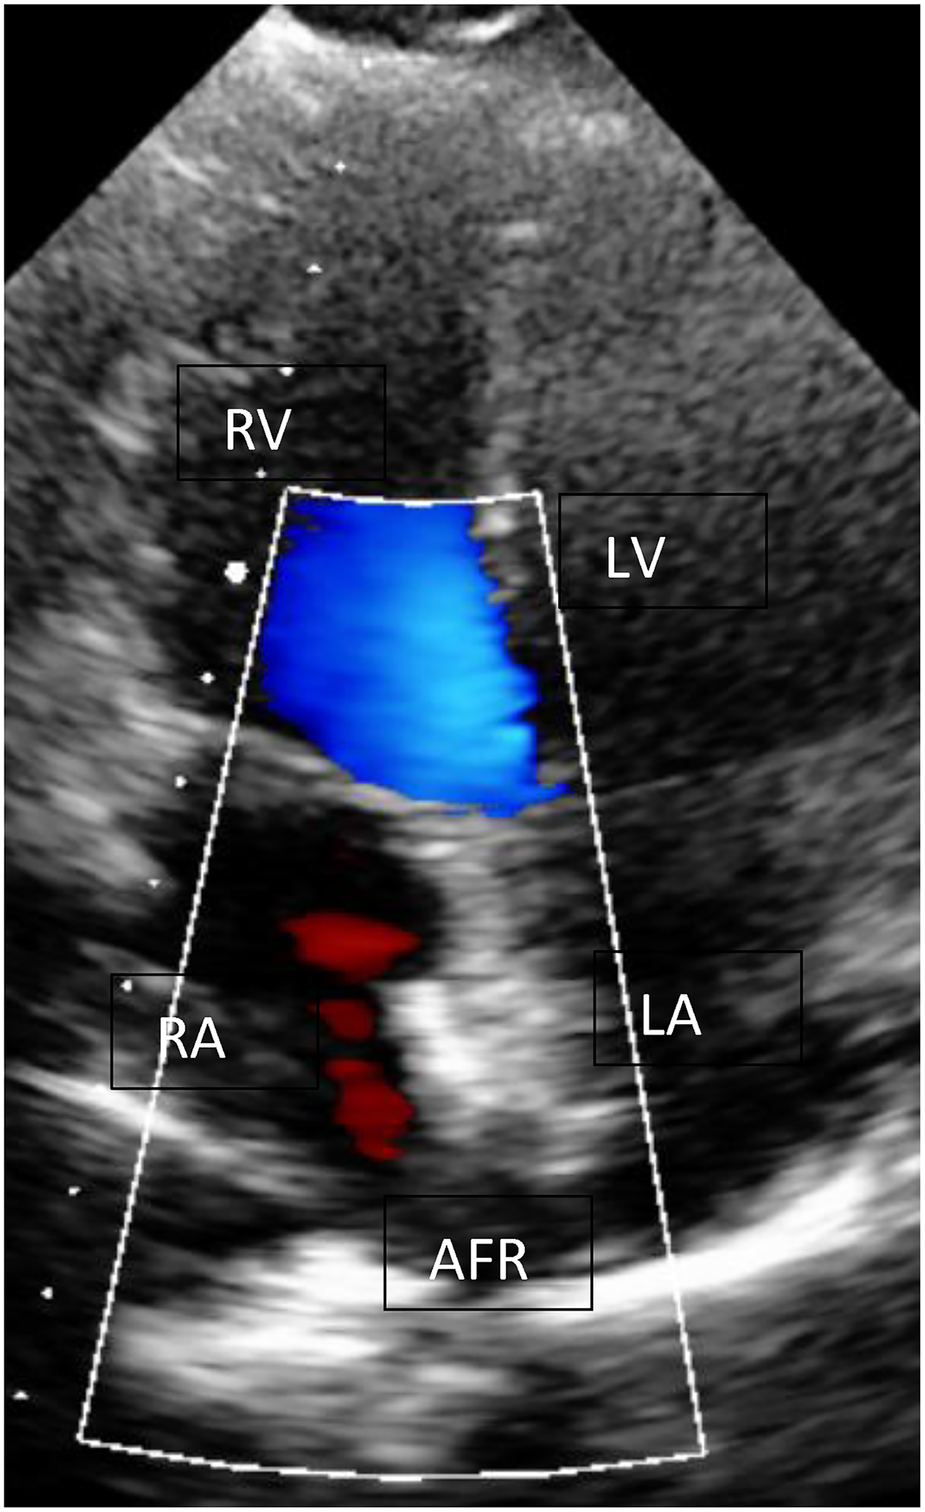

Due to the severity of the condition and the novel device, which was not CE approved then, we obtained informed consent, and the Ethical committee approved the off-label use of an 8ā mm AFR device. We performed the cardiac catheterisation under sedation. During induction, the child developed a PH crisis, which could be treated with Catecholamines and intravenous Prostacyclin. However, the second episode of a PH crisis occurred during device implantation. This time required a short period of resuscitation. Under the application of Adrenalin i.v. and Prostacyclin directly into the pulmonary artery, a stabilisation of the condition could be established. We perforated the intra-atrial septum with a Brockenorough transseptal puncture needle under the guidance of transesophageal echocardiography (TEE), the puncture hole was dilated, and a 12 Fr sheath was inserted over the interatrial communication into the left atrium so that 8ā mm AFR device could be deployed (FigureĀ 2). After confirming the correct position and checking the oxygen saturation level of greater than 85% and stable hemodynamic parameters, the device was completely and successfully released. The postinterventional echocardiography confirmed a right-to-left colour flow through the 8ā mm atrial communication (FigureĀ 3). After the intervention, anticoagulation with ASS was established.

Figure 3

AFR device (Occlutech, Germany) in echocardiography. AFR device (Occlutech, Germany) with L-R shunt at rest; RA, right atrium; LA, left atrium; LV, left ventricle; RV, right ventricle.